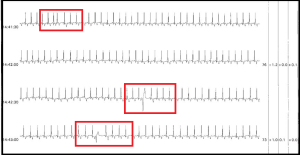

A Ventricular Ectopic Beat (VEB) or Premature Ventricular Contraction (PVC) is typically wider than the normal conduction of a Supraventricular Beat (> .12). PVC’s are generally originate in the ventricles from an ectopic focus rather than the atrium. A Multi-focal PVC can indicate a greater degree of irritability, electrical instability or disease state. The typical characteristics of a PVC can include no P wave, wide & bizarre shaped complex & often premature (early) with the presence of a complete compensatory pause.

Many clinical variations are seen. They may have P waves, as in the case of fusion beats. They may not have a compensatory pause, as in the case of interpolated PVC. They may not be wider than the patient’s normal complex, as in the case of chronic Bundle Branch Block (BBB). They may not be premature, as in the case of escape ventricular beats.

Single Isolated Premature Atrial Contraction (PAC) with 2 Isolated Premature Ventricular Contractions (PVC’s)